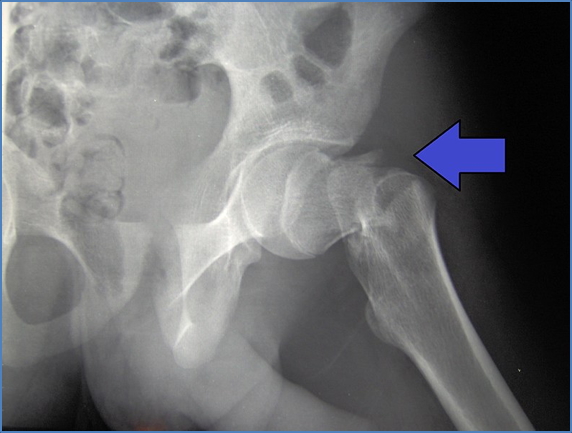

Lower Limb Fractures

- Femoral Shaft Fracture → Femoral nerve, Sciatic nerve, Femoral artery

- Neck of Femur Fracture → Sciatic nerve, Femoral nerve, Femoral artery

2. https://www.msdmanuals.com/home/multimedia/figure/fx_repairing_hip

- Hip Dislocation:

- Sciatic nerve

| Femoral | Femoral neck or shaft | ↓ Knee extension, hip flexion | Anterior thigh, medial lower leg |

| Obturator | Hip dislocation/fracture | ↓ Hip adduction | Medial thigh |

| Sciatic | Hip or femoral fracture | ↓ Knee flexion, foot/toe movement | Posterior leg & foot |